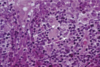

The wall of which cyst?

Periapical Cyst

Open clear areas = Cholesterol clefts where fat

used to be. Multinucleated cells (purple dots)

trying to break down cholesterol